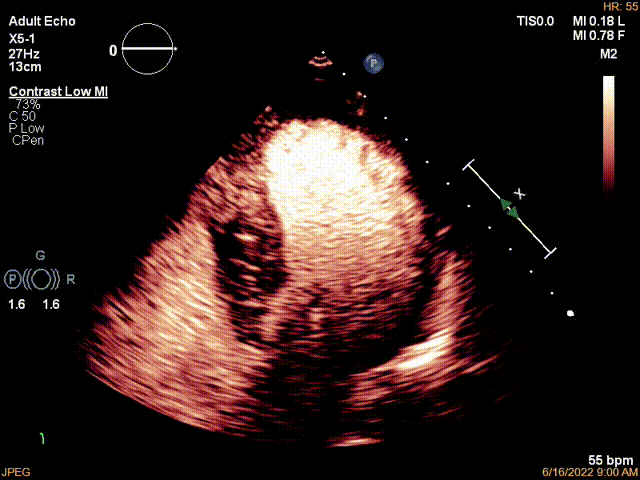

心尖四腔切面显示左室壁非对称性明显肥厚,左室有效容积明显减小